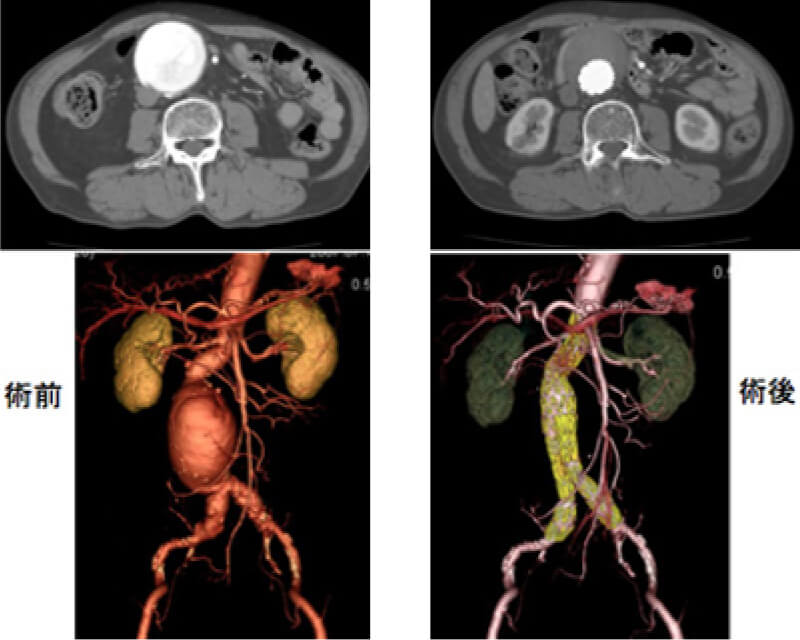

自作開窓型ステントグラフト内挿術

胸腹部大動脈瘤では(肝臓や膵臓、腎臓などへの)腹部内臓分枝起始部に動脈瘤が及んでいるため、単純なステントグラフト留置では治療できません。

欧米ではこのような症例への穴開きもしくは分枝付きステントグラフトが行われておりますが、本邦では保険適応外の治療となります。しかしながら、人工血管置換術を受けることが困難な状態の患者さんに対しては現実的には唯一の治療法となります。名古屋大学血管外科ではこのようなリスクの高い患者さんに対しては患者さんの同意の下、市販のステントグラフトに改造を加えることでステントグラフト治療を実施しています。

ステントグラフトに穴を開けておくことで、内臓分枝の血流を温存できます。